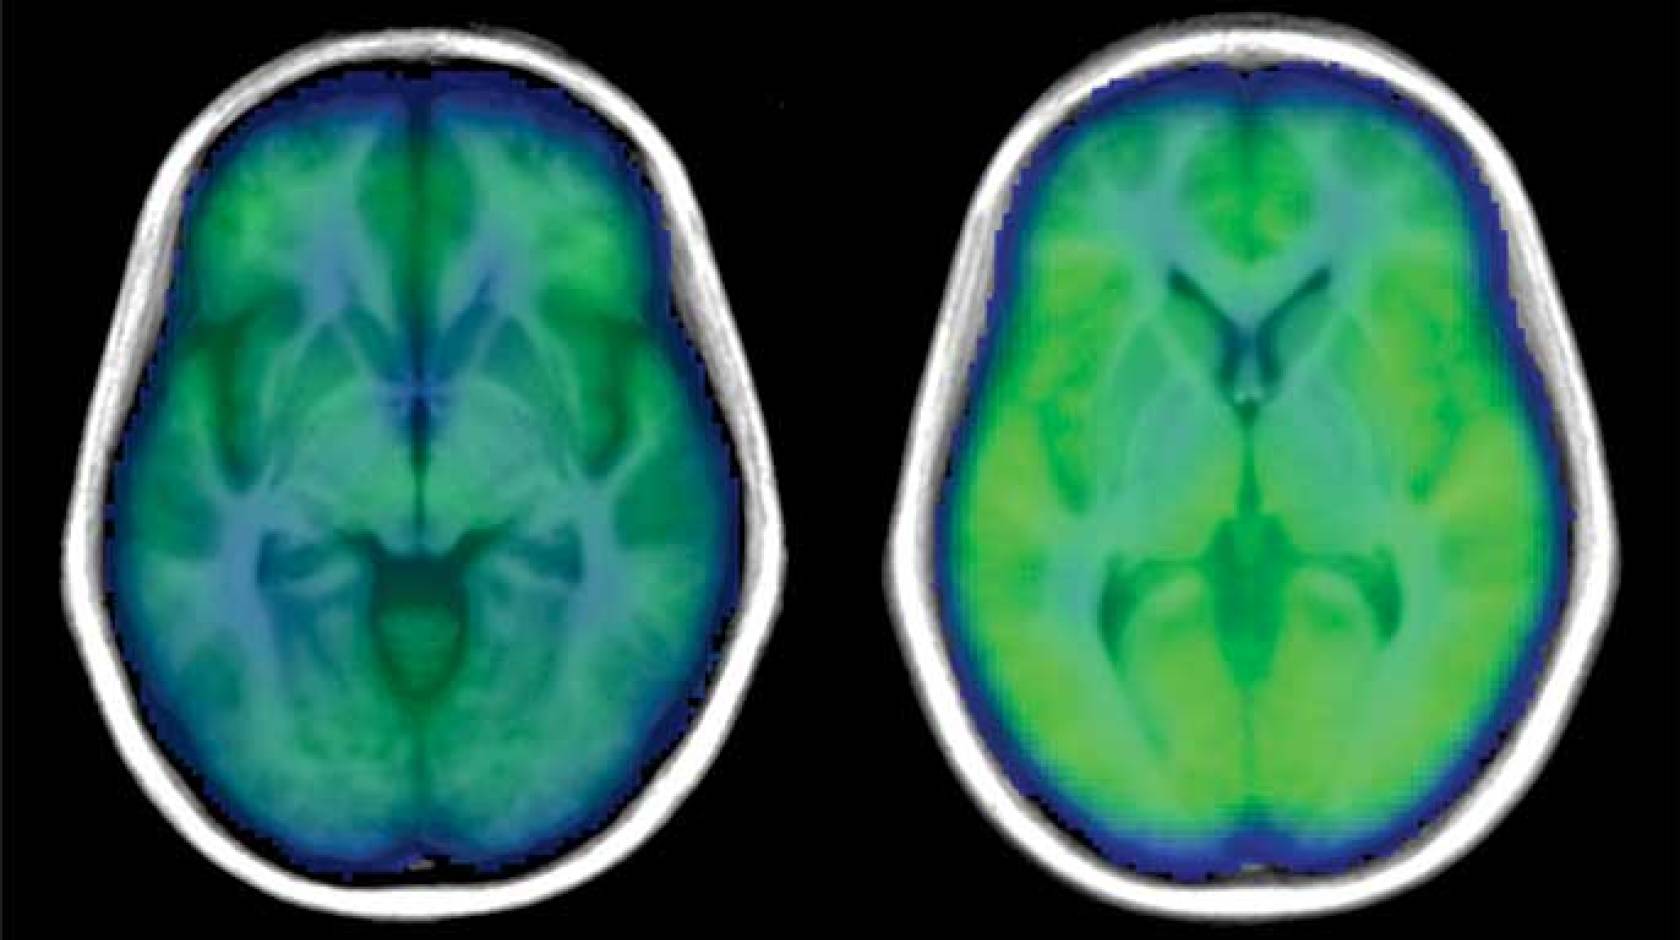

In the study, published Aug. 28 in the peer-reviewed journal PLOS ONE, researchers measured blood flow in the brain using a non-invasive MRI procedure: the global blood volume and oxygen dependent (BOLD) signal. This method is usually used to observe brain activity. Because previous research showed that poor regulation of blood in the brain might be a problem for people with sleep apnea, the researchers used the whole-brain BOLD signal to look at blood flow in individuals with and without obstructive sleep apnea (OSA).

“When we looked at the results, we didn’t see much difference between the participants with and without OSA in the Valsalva maneuver,” said Macey. “But for the hand-grip and cold-pressor challenges, people with OSA saw a much weaker brain blood flow response.”

The researchers believe that the reason there were differences in the sleep apnea patients during the hand-grip and cold pressor challenge was because the signals from the nerves in the arms and legs had to be processed through the high brain areas controlling sensation and muscle movement, which was slower due to the brain injury. On the other hand, the changes from the Valsalva are mainly driven by blood pressure signaling in the chest, and do not need the sensory or muscle-controlling parts of the brain.